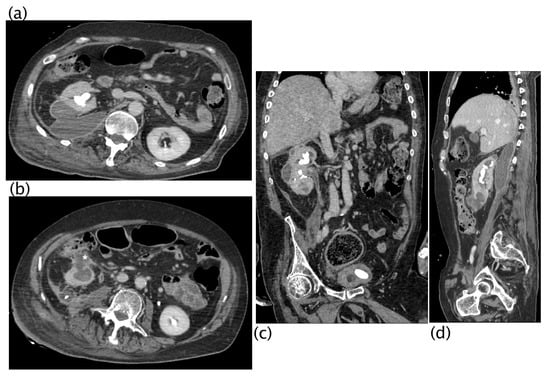

Xanthogranulomatous pyelonephritis Stage III—pararenal form. Non-enhanced CT examination: axial (a,b) and coronal MPR reconstruction (c,d). The right kidney is increased in volume with reduced parenchymal representation and a “contracted” appearance of the renal pelvis. The renal parenchyma is extremely thinned and characterized by the presence of multiple hypodense areas that cannot be better characterized without contrast agent. (a) Within the fluid collection at the anterior middle third of the kidney, a “layer” characterized by fluid (white asterisk) and adipose density (above white asterisk) can be noted, named “xanthoma” and characteristic of the disease. Staghorn lithiasis is present. No significant thickening of the perirenal fat tissue is noted. On the posterior profile of the kidney, a fistulous via with hydro-gas content is visible ((a), white arrow; (b)), which carries posteriorly into the psoas and dorsal muscles with fluid collection in the context of the muscle bundles. The fistulous via terminates in the subcutaneous flank soft tissues where fluid collection with gas is present ((d), MPR coronal).